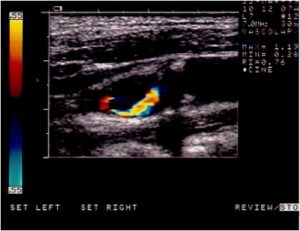

In caso di un restringimento importante delle arterie che portano il sangue al cervello denominate carotidi, in alternativa al tradizionale approccio chirurgico ( TEA o endoarteriectomia carotidea ) in casi selezionati, è possibile intervenire mediante l’introduzione, attraverso un’arteria principale, di un catetere che, posizionato a livello dell’ostruzione, dapprima permette il gonfiaggio di un palloncino che riaprirà il vaso e successivamente consentirà il posizionamento di una speciale maglia metallica ( STENT ) con la funzione di mantenere il vaso aperto nel tempo. Durante la manovra un filtro, posizionato a monte della stenosi, avrà il compito di bloccare e trattenere eventuali impurità che si dovessero generare nel corso della procedura stessa.